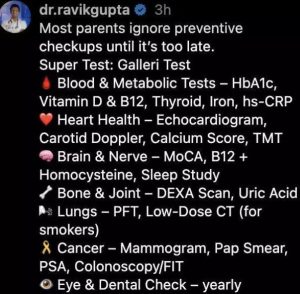

ನೀವು ಹೆತ್ತವರನ್ನು ಪ್ರೀತಿಸುತ್ತಿದ್ದರೆ, ಈ ಆರೋಗ್ಯ ಪರೀಕ್ಷೆಗಳನ್ನು ಮಾಡಿಸಿಕೊಳ್ಳಬೇಕು ಎಂದು ಡಾ. ರವಿ ಗುಪ್ತಾ ಹೇಳಿದ್ದಾರೆ. ಗ್ಯಾಲರಿ ಪರೀಕ್ಷೆಗಳು – ರಕ್ತವು 50+ ರೀತಿಯ ಕ್ಯಾನ್ಸರ್ಗಳನ್ನು ಪತ್ತೆ

ನೀವು ಹೆತ್ತವರನ್ನು ಪ್ರೀತಿಸುತ್ತಿದ್ದರೆ, ಈ ಆರೋಗ್ಯ ಪರೀಕ್ಷೆಗಳನ್ನು ಮಾಡಿಸಿಕೊಳ್ಳಬೇಕು ಎಂದು ಡಾ. ರವಿ ಗುಪ್ತಾ ಹೇಳಿದ್ದಾರೆ. ಗ್ಯಾಲರಿ ಪರೀಕ್ಷೆಗಳು – ರಕ್ತವು 50+ ರೀತಿಯ ಕ್ಯಾನ್ಸರ್ಗಳನ್ನು ಪತ್ತೆ